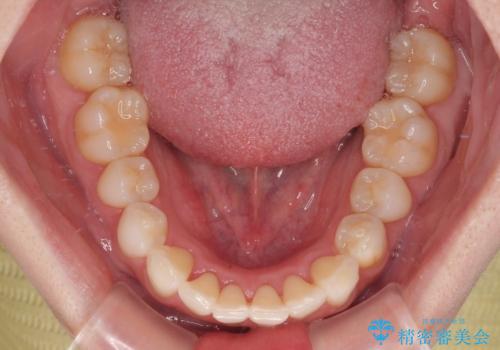

- 上下前歯の叢生を気にして来院された患者様です。

軽度な叢生であり、安価で短期間の治療を規模されていたため、インビザライン・モデレートを用いて矯正治療を行うこととしました。